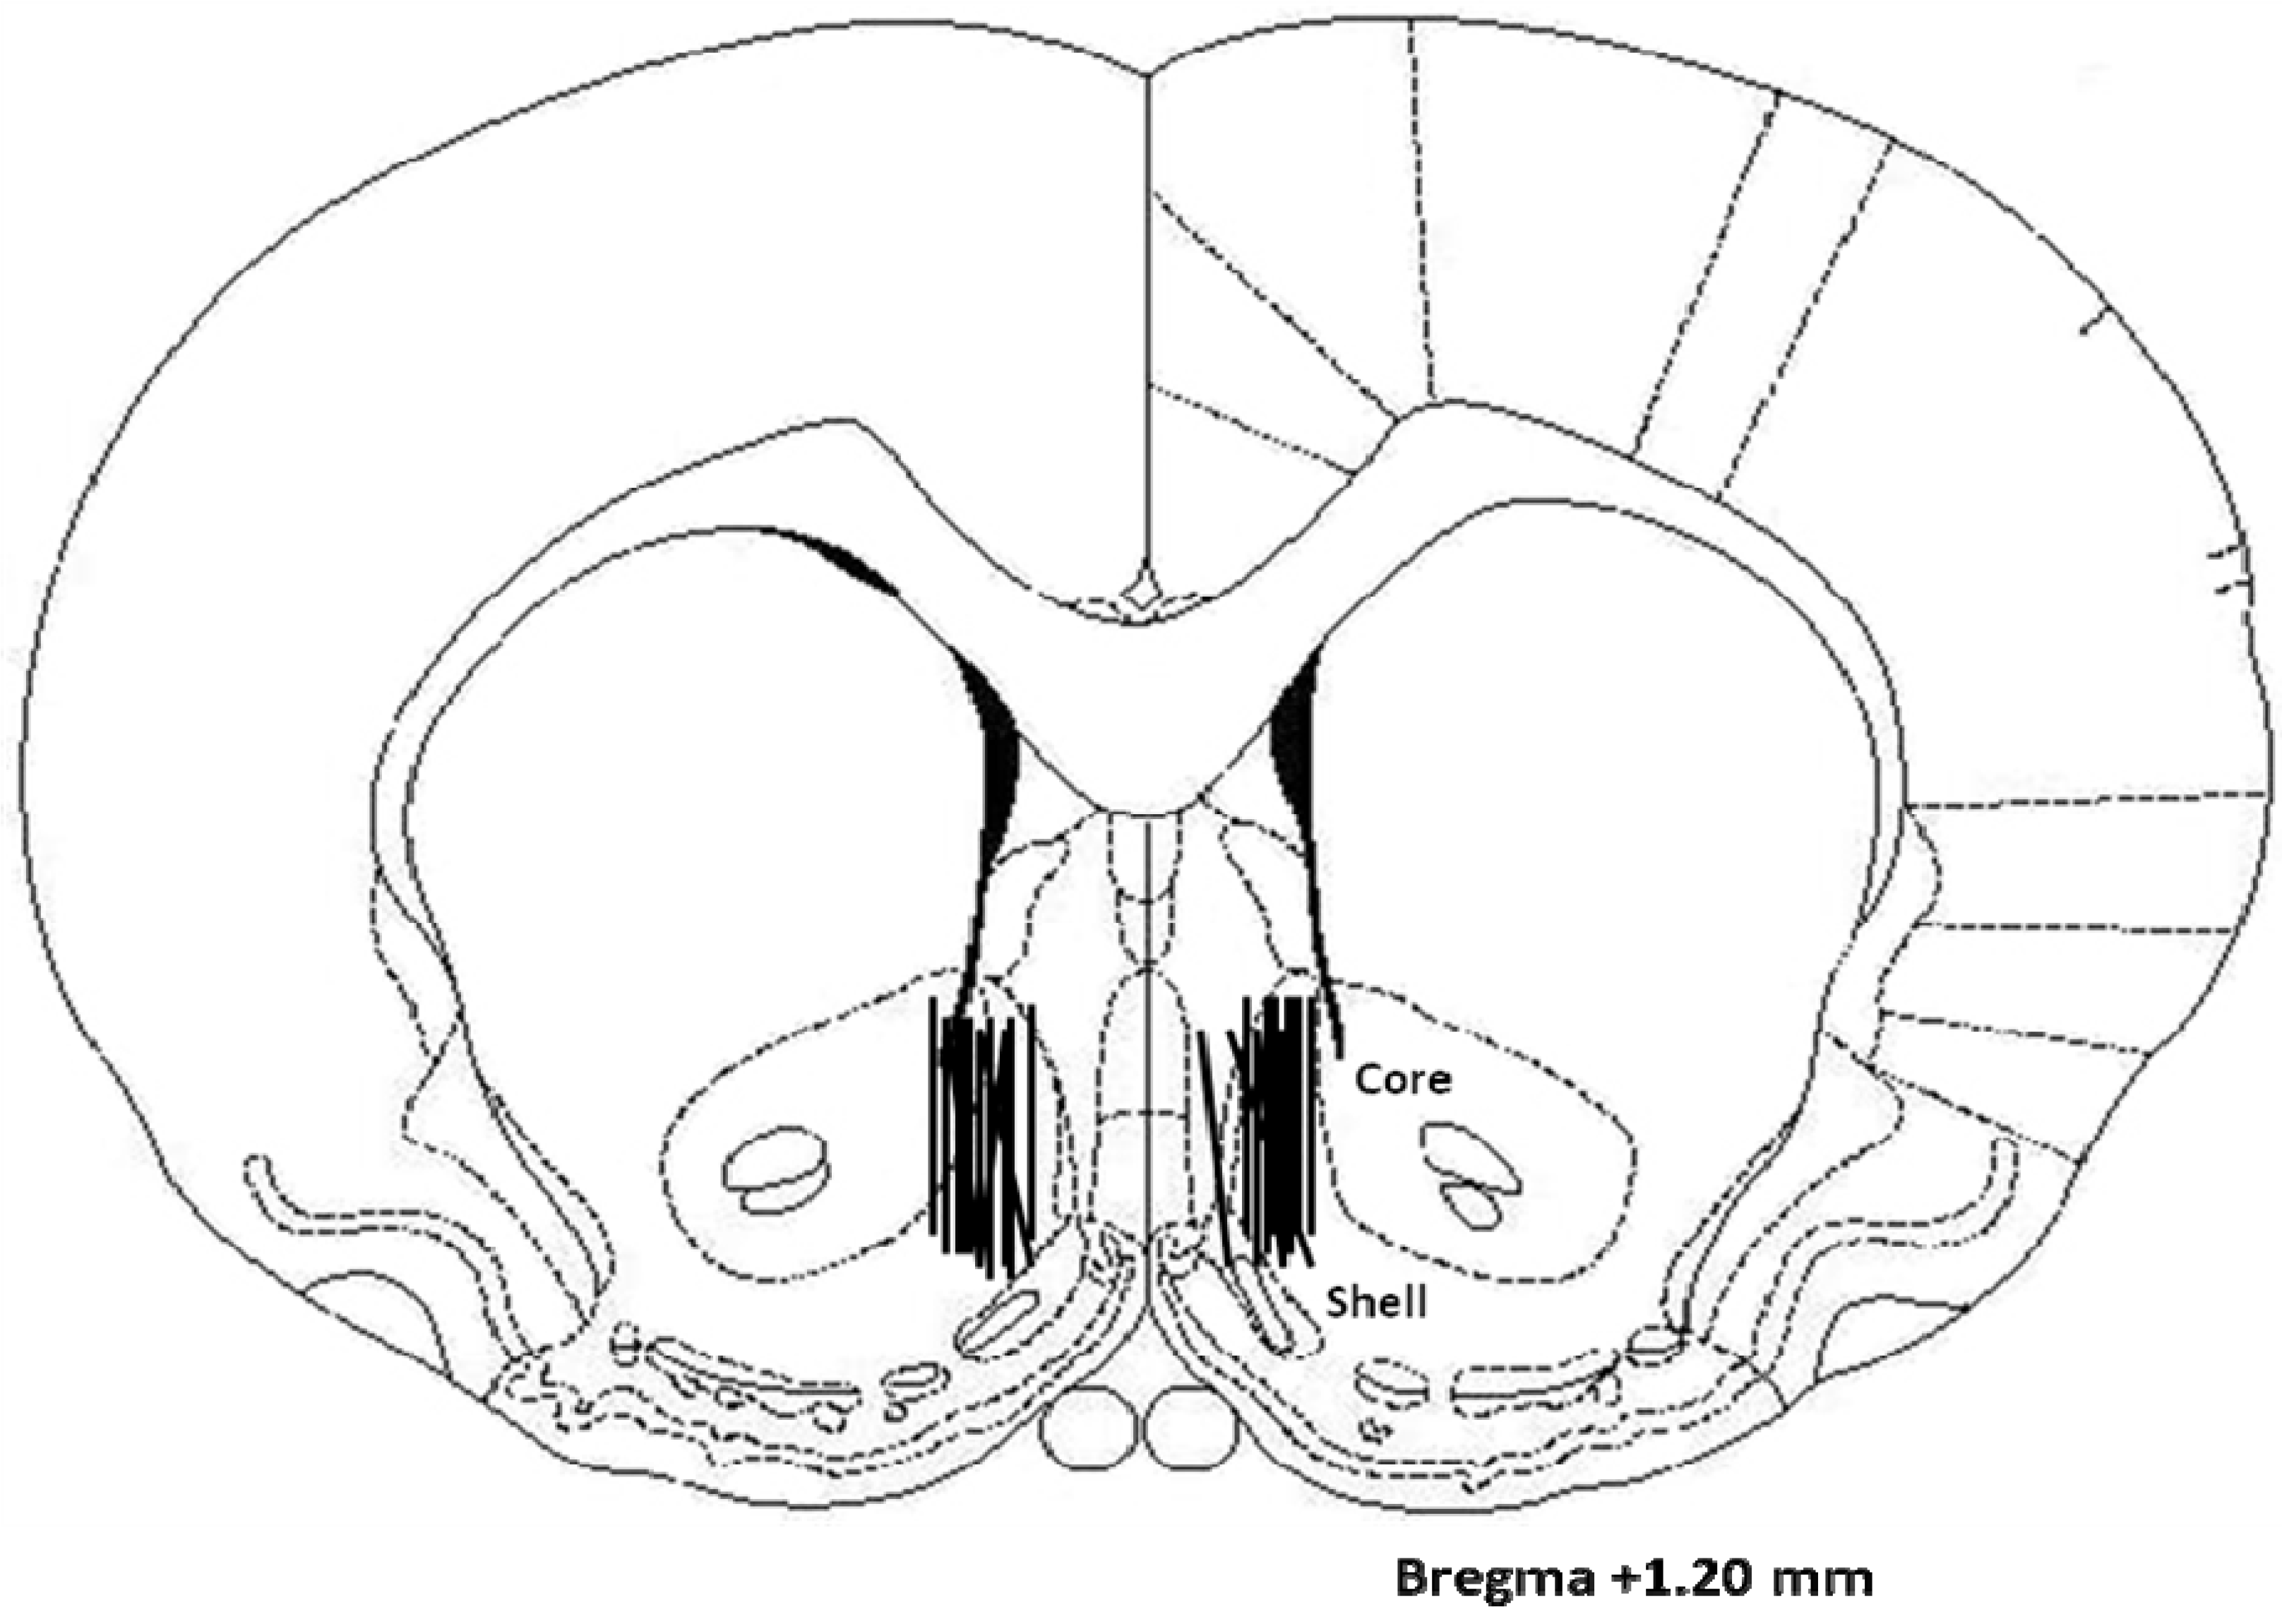

2.3. Histology

4.6. Histology